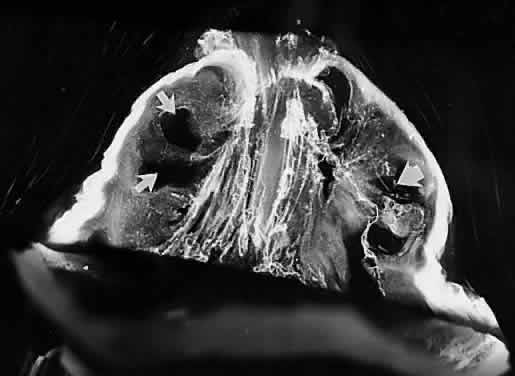

The pathogenesis of retinopathy of prematurity (ROP) begins with birth prior to complete maturation and development of the peripheral retina. Postnatal oxygen administration triggers retinal vasoconstriction with endothelial cell necrosis and vaso-obliteration in response to hyperoxia.127–129 After the discontinuation of supplemental oxygen, arterial pO2 levels return to normal and the obliterated (or at best, highly constricted) vessels are not adequately reperfused, causing the peripheral retina they subserve to become ischemic and release neovascular growth factors. An alternative hypothesis of pathogenesis proposes that spindle cells in the immature peripheral retina are stimulated by excessive amounts of reactive oxygen species, whether related to oxygen therapy and subsequent relative hypoxia or other metabolic circumstances, to release angiogenic growth factors.130 In either case, the result is migration and proliferation of capillary endothelial cells that form new blood vessels at the posterior ridge of tissue between the vascularized and avascular retina. This results in neovascularization arising from the ridge that demarcates the developed posterior retina from the immature peripheral retina (Fig. 6). The new vessels grow into the vitreous body, onto and into the plane that demarcates the interface between the gel vitreous posteriorly (overlying developed retina) and the liquid vitreous anteriorly (overlying immature retina). While somewhat similar to neovascularization in diabetic retinopathy,131 the new vessels in ROP grow farther anteriorly and with greater exuberance. This is perhaps because of the participation of cells of the ocular fetal vasculature, whose apoptosis has been retarded or arrested by the presence of high levels of VEGF.132

Fig. 6. Vitreous pathology in retinopathy of prematurity. The lack of peripheral retinal development, most prominent temporally, results in abnormal secondary vitreous development in this region. Thus, there is liquid vitreous rather than gel in the peripheral fundus. The interface between the normal gel vitreous posteriorly and the liquid vitreous anteriorly causes instability with traction upon the ridge of cells from which new vessels proliferate. The proliferation and membrane formation follows the interface plane between the gel and liquid vitreous compartments, oriented toward the edge of the lens. Traction at the ridge stimulates further vessel proliferation, traction upon the peripheral retina, and ultimately hemorrhage and/or retinal detachment. *, lens; G, gel vitreous (posterior); L, liquid vitreous (anterior). (Courtesy of Maurice Landers, MD)

There are no clearly identified vitreous changes during stages I and II of acute ROP, although this may simply be due to our present inability to detect such abnormalities.133 Indeed, the abundance of reactive oxygen species in the retina and vitreous of premature infants could induce widespread vitreous liquefaction.82 There are also likely to be localized areas of liquid vitreous, particularly at the periphery. At surgery for stage IV-A ROP with retinal detachment, there is a trough in the periphery.134 This structure is most likely the consequence of underlying immature retina in the periphery, with consequent lack of typical gel vitreous synthesis, normally a Müller cell function, overlying the immature retina. The liquid vitreous trough is probably present early in the natural history of disease but goes undetected by present vitreous imaging techniques.133 Such disruption of normal vitreous composition and structure probably alters a number of physiologic processes within the vitreous, including the ability of vitreous to inhibit cellular and vascular invasion.135 Furthermore, the interface between posterior gel vitreous and peripheral liquid vitreous at the ridge causes vitreous traction to be exerted at the retinal ridge.

In stage III ROP, new blood vessels extend from the inner retina into the vitreous cortex. The cortex, overlying the rear guard of differentiated capillary endothelial cells, becomes opaque and contains linear, fibrous structures adjacent to a large pocket of liquid vitreous.136 In advancing from stage III to stage IV, the neovascular tissue arising from the rear guard grows through the vitreous body toward Wiegert's ligament on the posterior lens capsule.136 This configuration of neovascularization is probably the result of cell migration and proliferation along the walls of the future Cloquet's canal or the tractus hyaloideus of Eisner. Cells of the primary vitreous likely contribute to the formation of the dense central vitreous stalk and retrolental membrane seen in the cicatricial stage, because these cells could also undergo migratory and proliferative responses to intraocular angiogenic stimuli.

Familial Exudative Vitreoretinopathy

This autosomal (long arm of chromosome 11) dominant (sporadic cases of X-linked recessive disease have been reported) vitreoretinopathy features inner retinal non-perfusion, neovascularization and retinal detachment. The histologic vascular changes are indistinguishable from those of ROP, however, patients with familial exudative vitreoretinopathy (FEVR) have no history of prematurity or neonatal oxygen exposure.137,138 Mild forms of the disease are characterized by areas of peripheral nonperfusion, cystoid degeneration, and condensation of the temporal vitreous base and vitreous membranes. Moderate forms involve vitreous base traction, flat or elevated neovascularization, and retinal or subretinal exudates. The severe forms of FEVR, which usually cause vision loss, are similar to cicatricial ROP, featuring iris atrophy, neovascular glaucoma, cataracts, falciform retinal folds, macular heterotopia, and retinal detachment.139,140 In a recent series141 of 28 patients who underwent vitreoretinal surgery, 25 had rhegmatogenous and 2 had traction retinal detachments. Vitreoretinal adhesion was so strong in the avascular peripheral retina that iatrogenic retinal breaks occurred in 22 of 28 eyes during surgery. It is quite plausible that in similar fashion to ROP, FEVR has poorly developed vitreous overlying the nonperfused, and therefore immature, peripheral retina. The instability between the well-developed posterior gel vitreous and the liquefied peripheral anterior vitreous (Fig. 6) probably exerts traction upon the retina inducing the rhegmatogenous and tractional detachments.